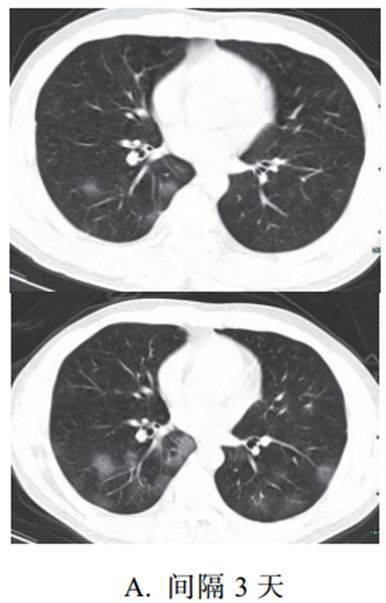

二、进展期征象

新冠肺炎大多数病例进展迅速,复查 CT 影像发生明显变化

表现为病灶数目明显增多,范围明显扩大,密度增高,病灶分布由外周向中央推进

根据既往 SARS 病理学机制,提示为肺泡腔内聚集大量细胞渗出液、间质内血管扩张渗出;肺泡连通起来形成融合态势(图 2-11)